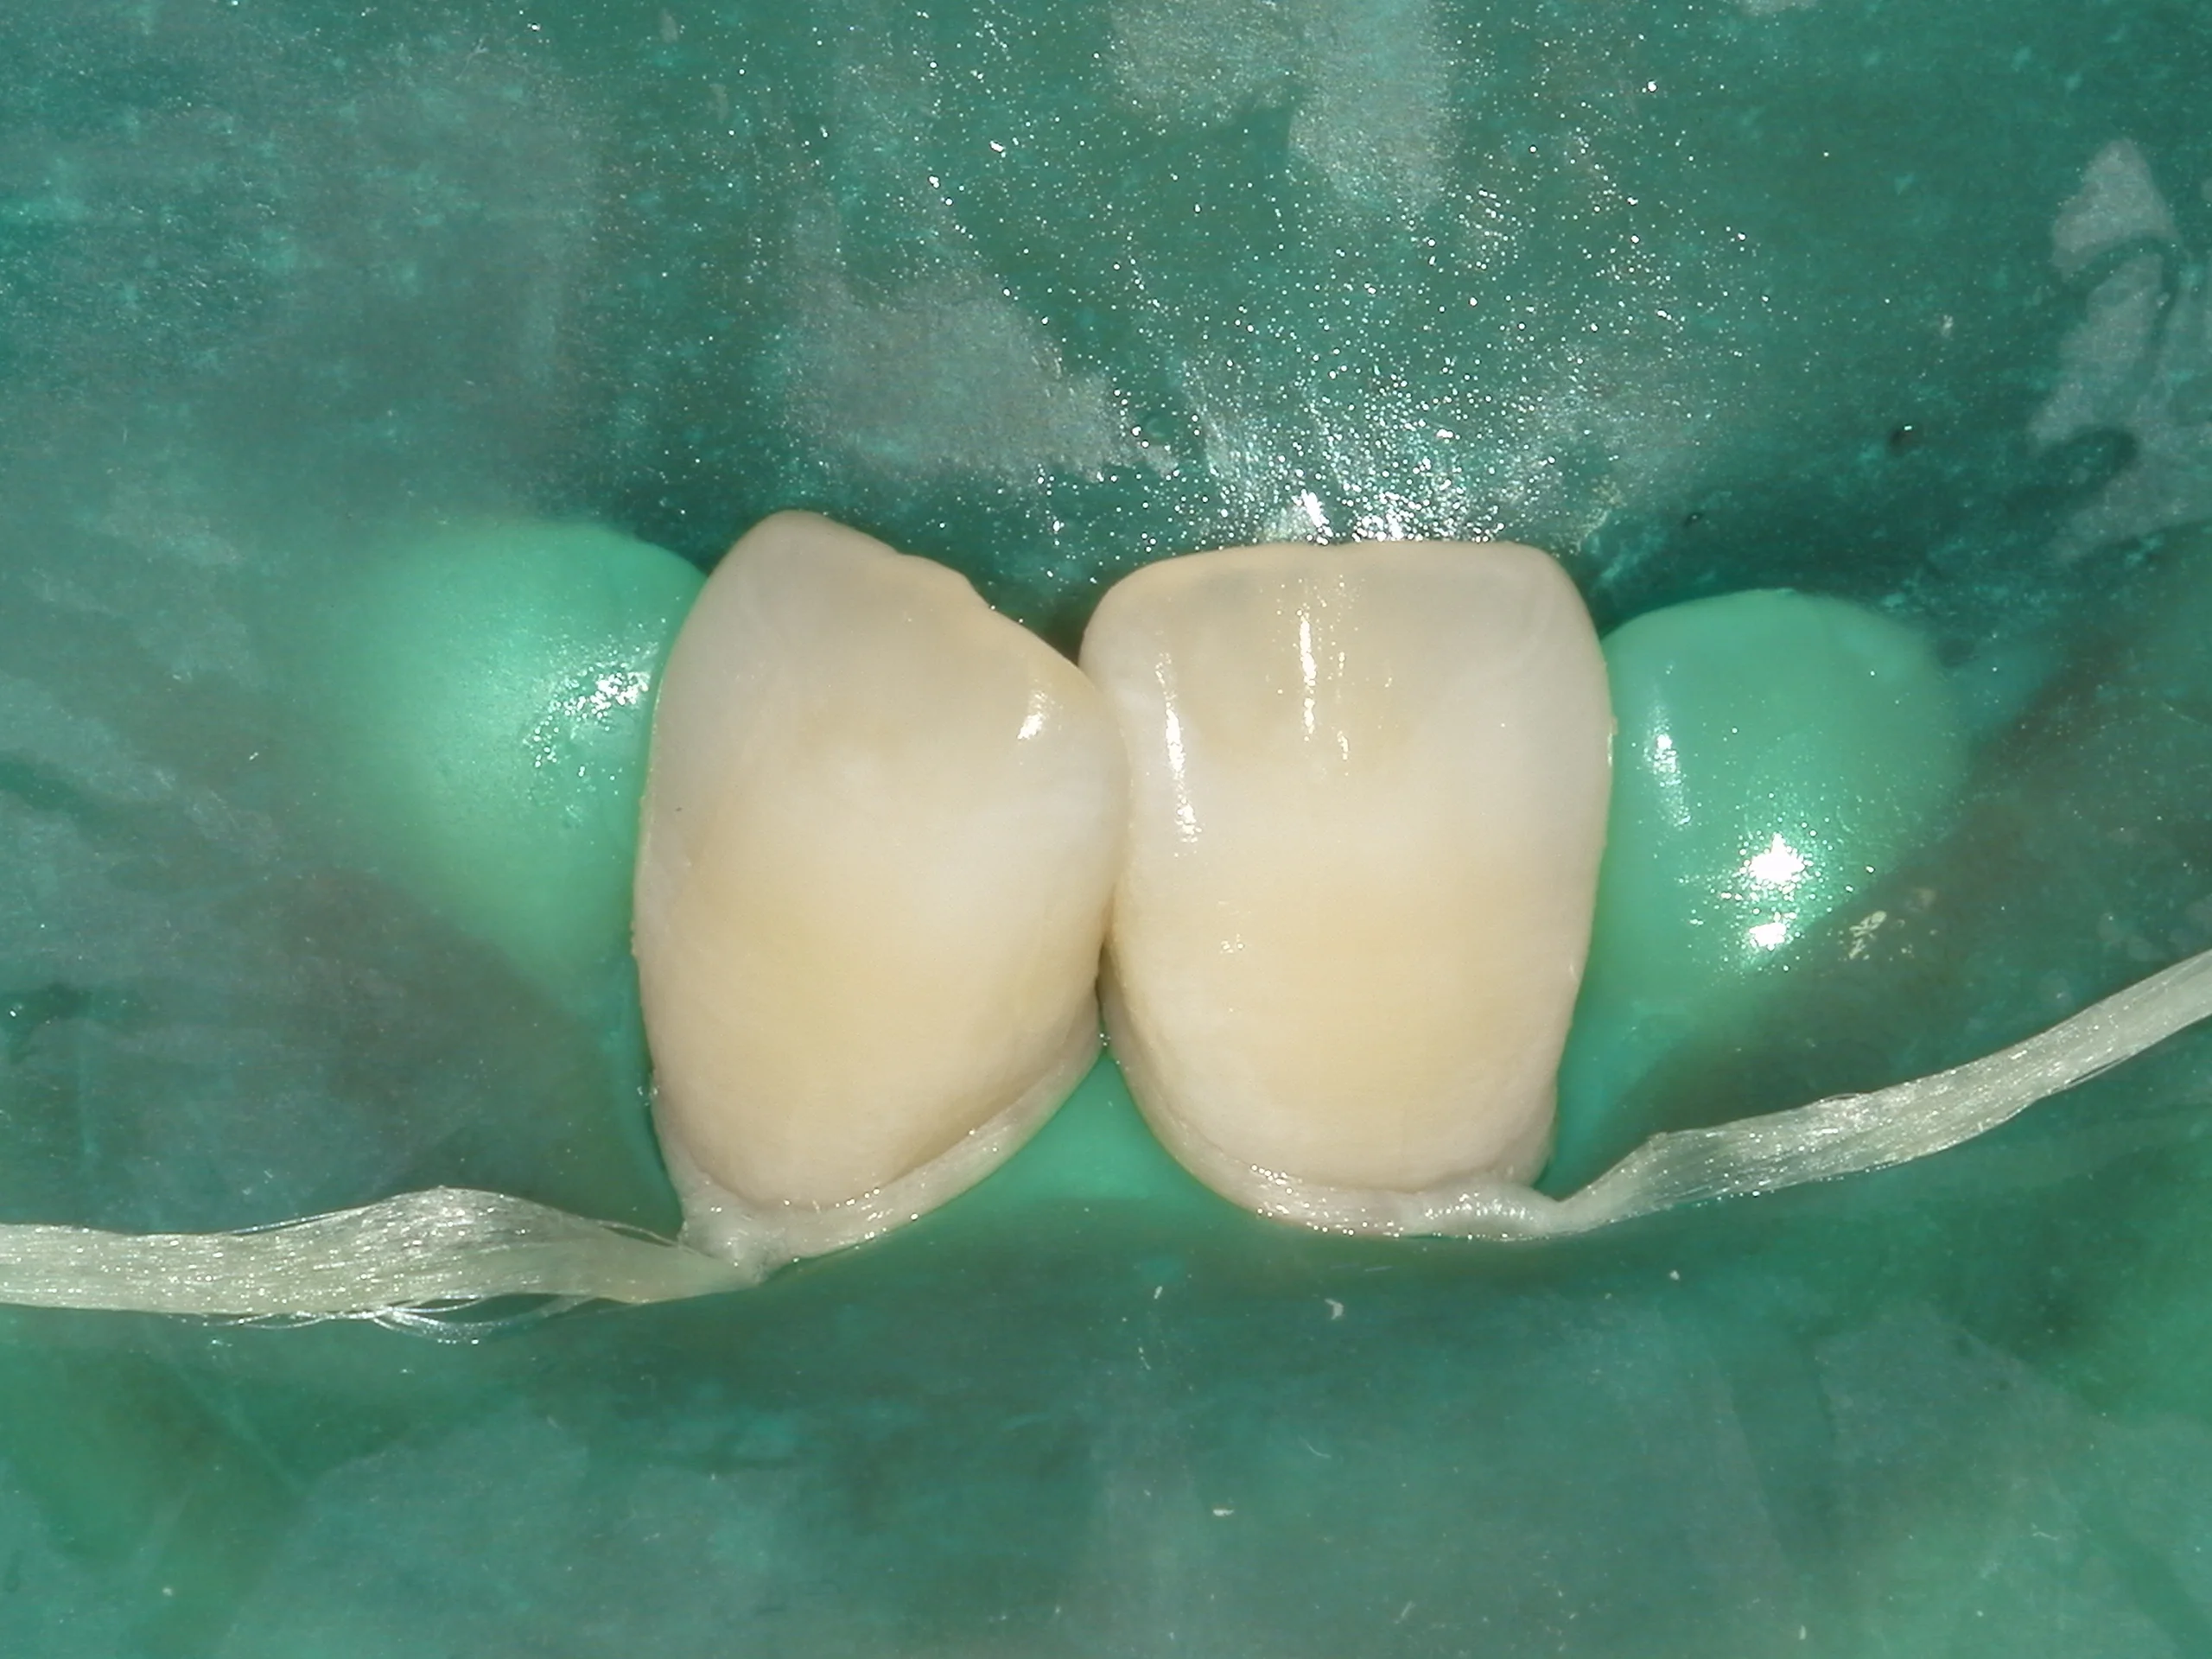

そしてホワイトスポットが消えたなと肉眼で判断出来たら、そこにICONを染み込ませて固めます。

固めたのがこちらになります。

ラバーダムを外した術前術後の写真はこちらになります。

随分と目立たなくなったのが分かるかと思います。